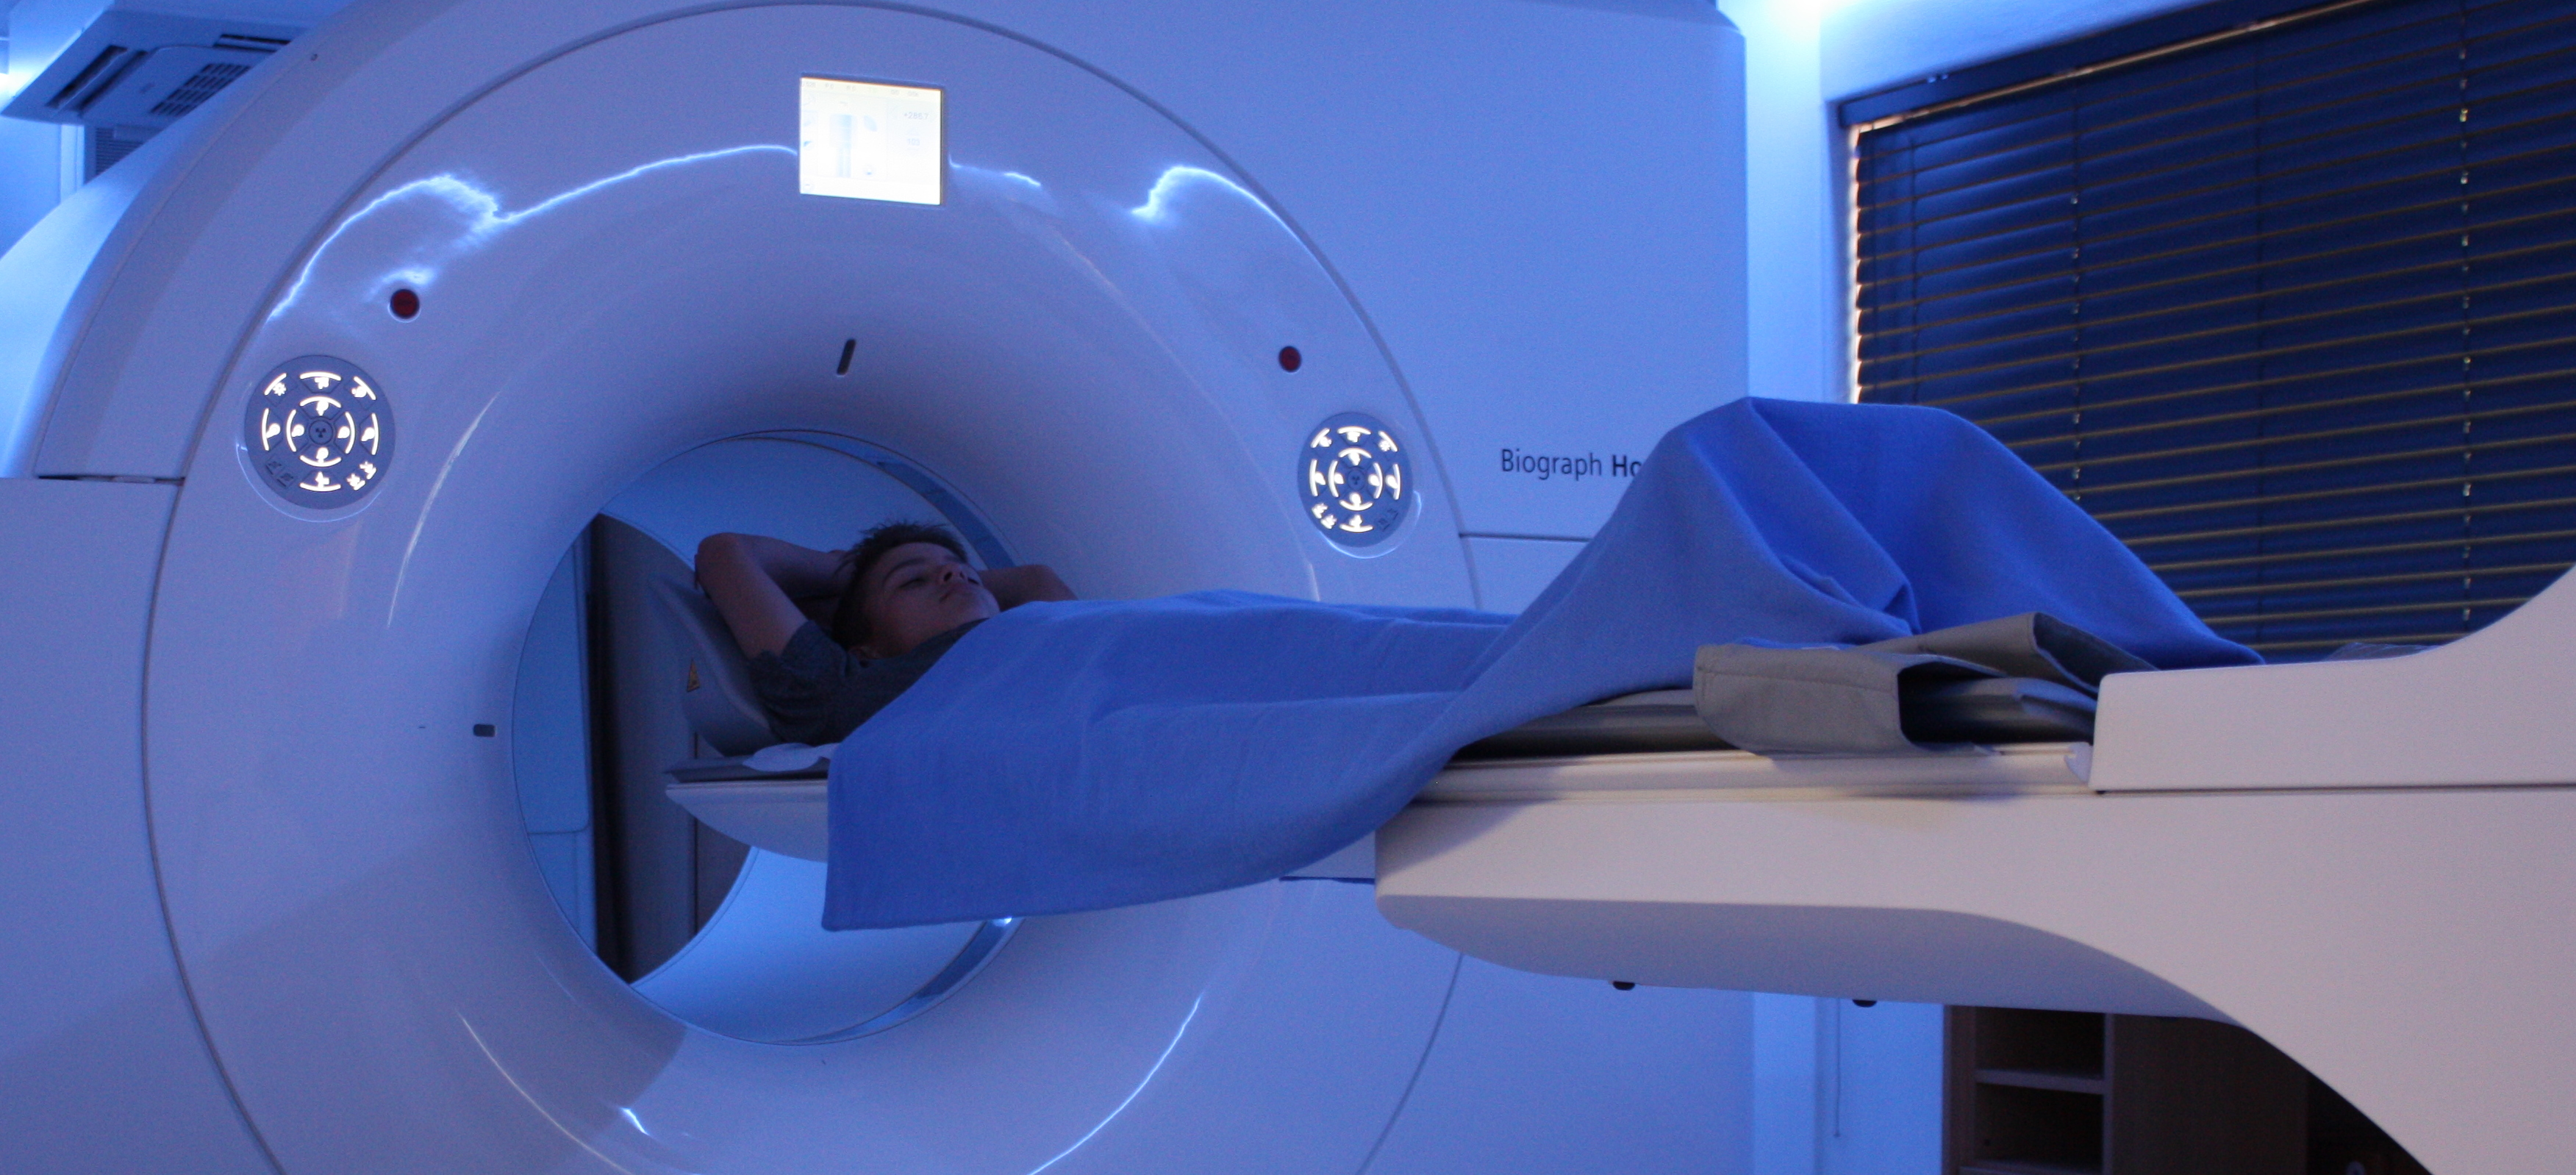

This advanced nuclear imaging technique combines positron emission tomography (PET) and computed tomography (CT) into one machine. A PET/CT scan reveals information about both the structure and function of cells and tissues in the body during a single imaging session.

Read MoreThe last few years have seen unprecedented advances in medical imaging techniques, allowing doctors an extraordinary view into the human body and the opportunity to fine-tune treatment. PET-CT is well established internationally as the ‘Gold Standard’ for the assessment of the extent of cancer spread in the body as well as the assessment of cancer treatment.